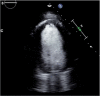

A 72-year-old woman with no history of coronary artery disease presented with an acute left middle cerebral artery stroke and was found to have a large left ventricular pseudoaneurysm measuring 8.7 × 7.6 cm and 2 large left ventricular thrombi, the source of her systemic embolization. Despite initial medical management, she developed refractory New York Heart Association functional class III heart failure, uncontrolled atrial fibrillation, and further enlargement of her pseudoaneurysm to 5.5 × 10.6 × 9.2 cm. She underwent urgent aneurysmectomy. Left ventricular pseudoaneurysms are rare and most commonly occur following an acute myocardial infarction when a ventricular free-wall rupture is contained by pericardium or thrombi. Historically, left ventricular angiography displaying a lack of an overlying coronary artery was the gold standard for diagnosis. Now, noninvasive imaging such as computed tomography, magnetic resonance imaging, and echocardiogram with ultrasound-enhancing agent, are reliable diagnostic tools. They can distinguish a pseudoaneurysm from a true left ventricular aneurysm using characteristic findings such as a narrow aneurysm neck, bidirectional doppler flow between the pseudoaneurysm and the left ventricle, and abrupt changes in the cardiac wall structures. Progressive dilation, wall thinning, and dyskinesis can result in refractory heart failure, arrhythmias, and thrombi formation from venous stasis. Pseudoaneurysms have a 30% to 45% risk of rupture and can be treated with left ventricular aneurysmectomy.